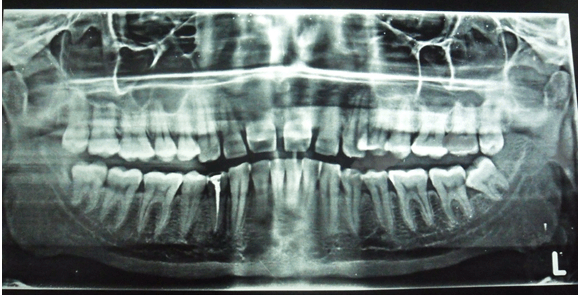

Based on the history and clinical examination, a provisional diagnosis was given as mucoepidermoid carcinoma. Differential diagnosis was given as adenoid cystic carcinoma, carcinoma involving hard palate and carcinoma involving maxillary sinus. Blood investigations were done in which there was no abnormality except the raise in erythrocyte sedimentation rate. Panoramic radiograph was not suggestive of any pathology near hard palate (Figure 2). Hence, advanced imaging computed tomography scan was advised which revealed area of altered attenuation showing heterogeneous enhancement on contrast. It also revealed soft tissue attenuation of left maxillary sinus (Figure 3). Based on these findings, the radiographic differential diagnosis was as carcinoma involving the hard palate.

Figure 2: Panoramic radiograph was not suggestive of any pathology near hard palate.